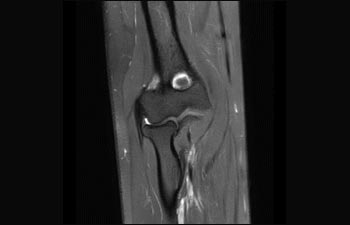

Elbow overview